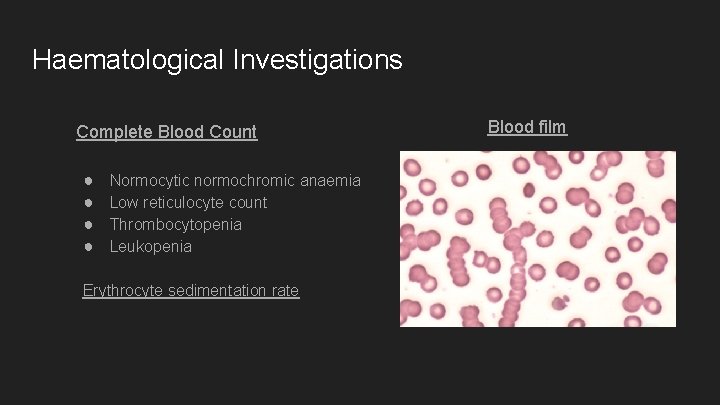

Haematological Investigations Complete Blood Count ● ● Normocytic normochromic anaemia Low reticulocyte count Thrombocytopenia Leukopenia Erythrocyte sedimentation rate Blood film